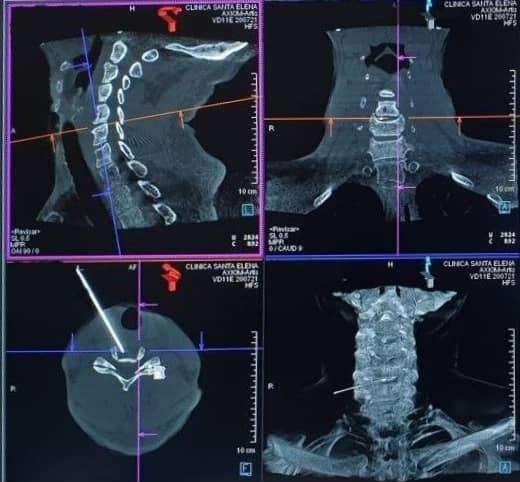

• Tomografía computarizada (TC): A veces se utiliza para obtener imágenes detalladas de la columna vertebral si no se puede realizar una resonancia magnética.

Esta novedosa técnica consiste en aplicar un láser a través de una aguja, directamente en el interior de los discos herniados. El tratamiento está automatizado en varios ciclos, produciendo una termocoagulación del núcleo que disuelve y descomprime los nervios adyacentes en cuestión de minutos.

La temperatura se mantiene estable por debajo de los 50º para evitar cualquier daño a los nervios o estructuras colindantes. Es compatible con el uso de otras técnicas intradiscales como el ozono, y no contraindica la posibilidad de cirugía si fuera necesaria.

El canal láser se aplica en el mismo núcleo de la hernia, evaporando el material en pocos minutos para reducir la presión interna.